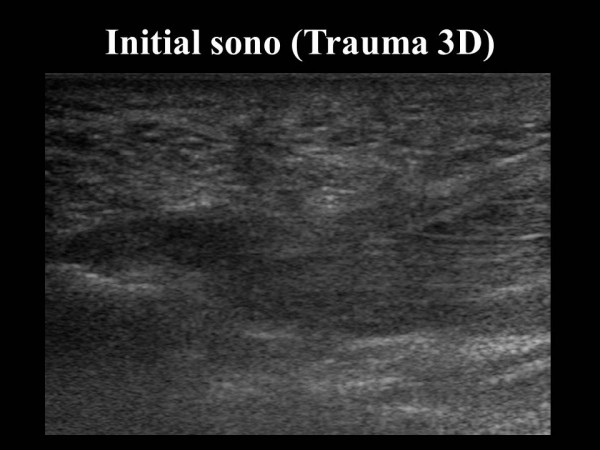

논문 및 학술활동 족부 족저 근막 파열 환자에서의 초음파 소견 20.08.24 15:31 1,754 족저 근막 파열 환자에서의 초음파 소견 : 2017년 대한정형외과 초음파학회 추계학술대회 발바닥 통증의 원인, 족저근막염과 근막파열의 감별법 연구 이전글 양측 족부의 여러 부위에 동통성 종괴를 호소하는 58세 남자 환자 case report 20.08.24 다음글 Treatment of Hallux Varus Deformity with a Concomitant Osteoarthritis 20.08.24 목록